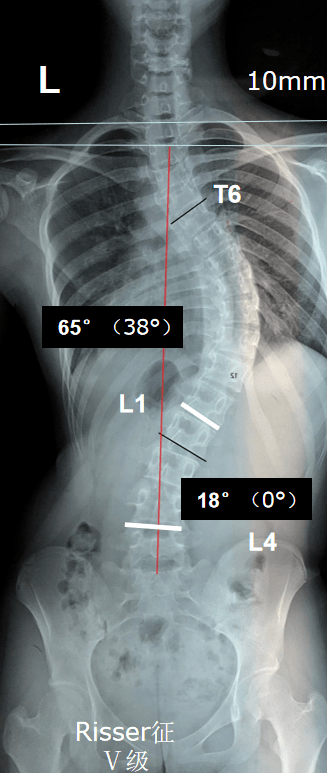

手術前

手術前X光片,可見明顯脊柱側彎